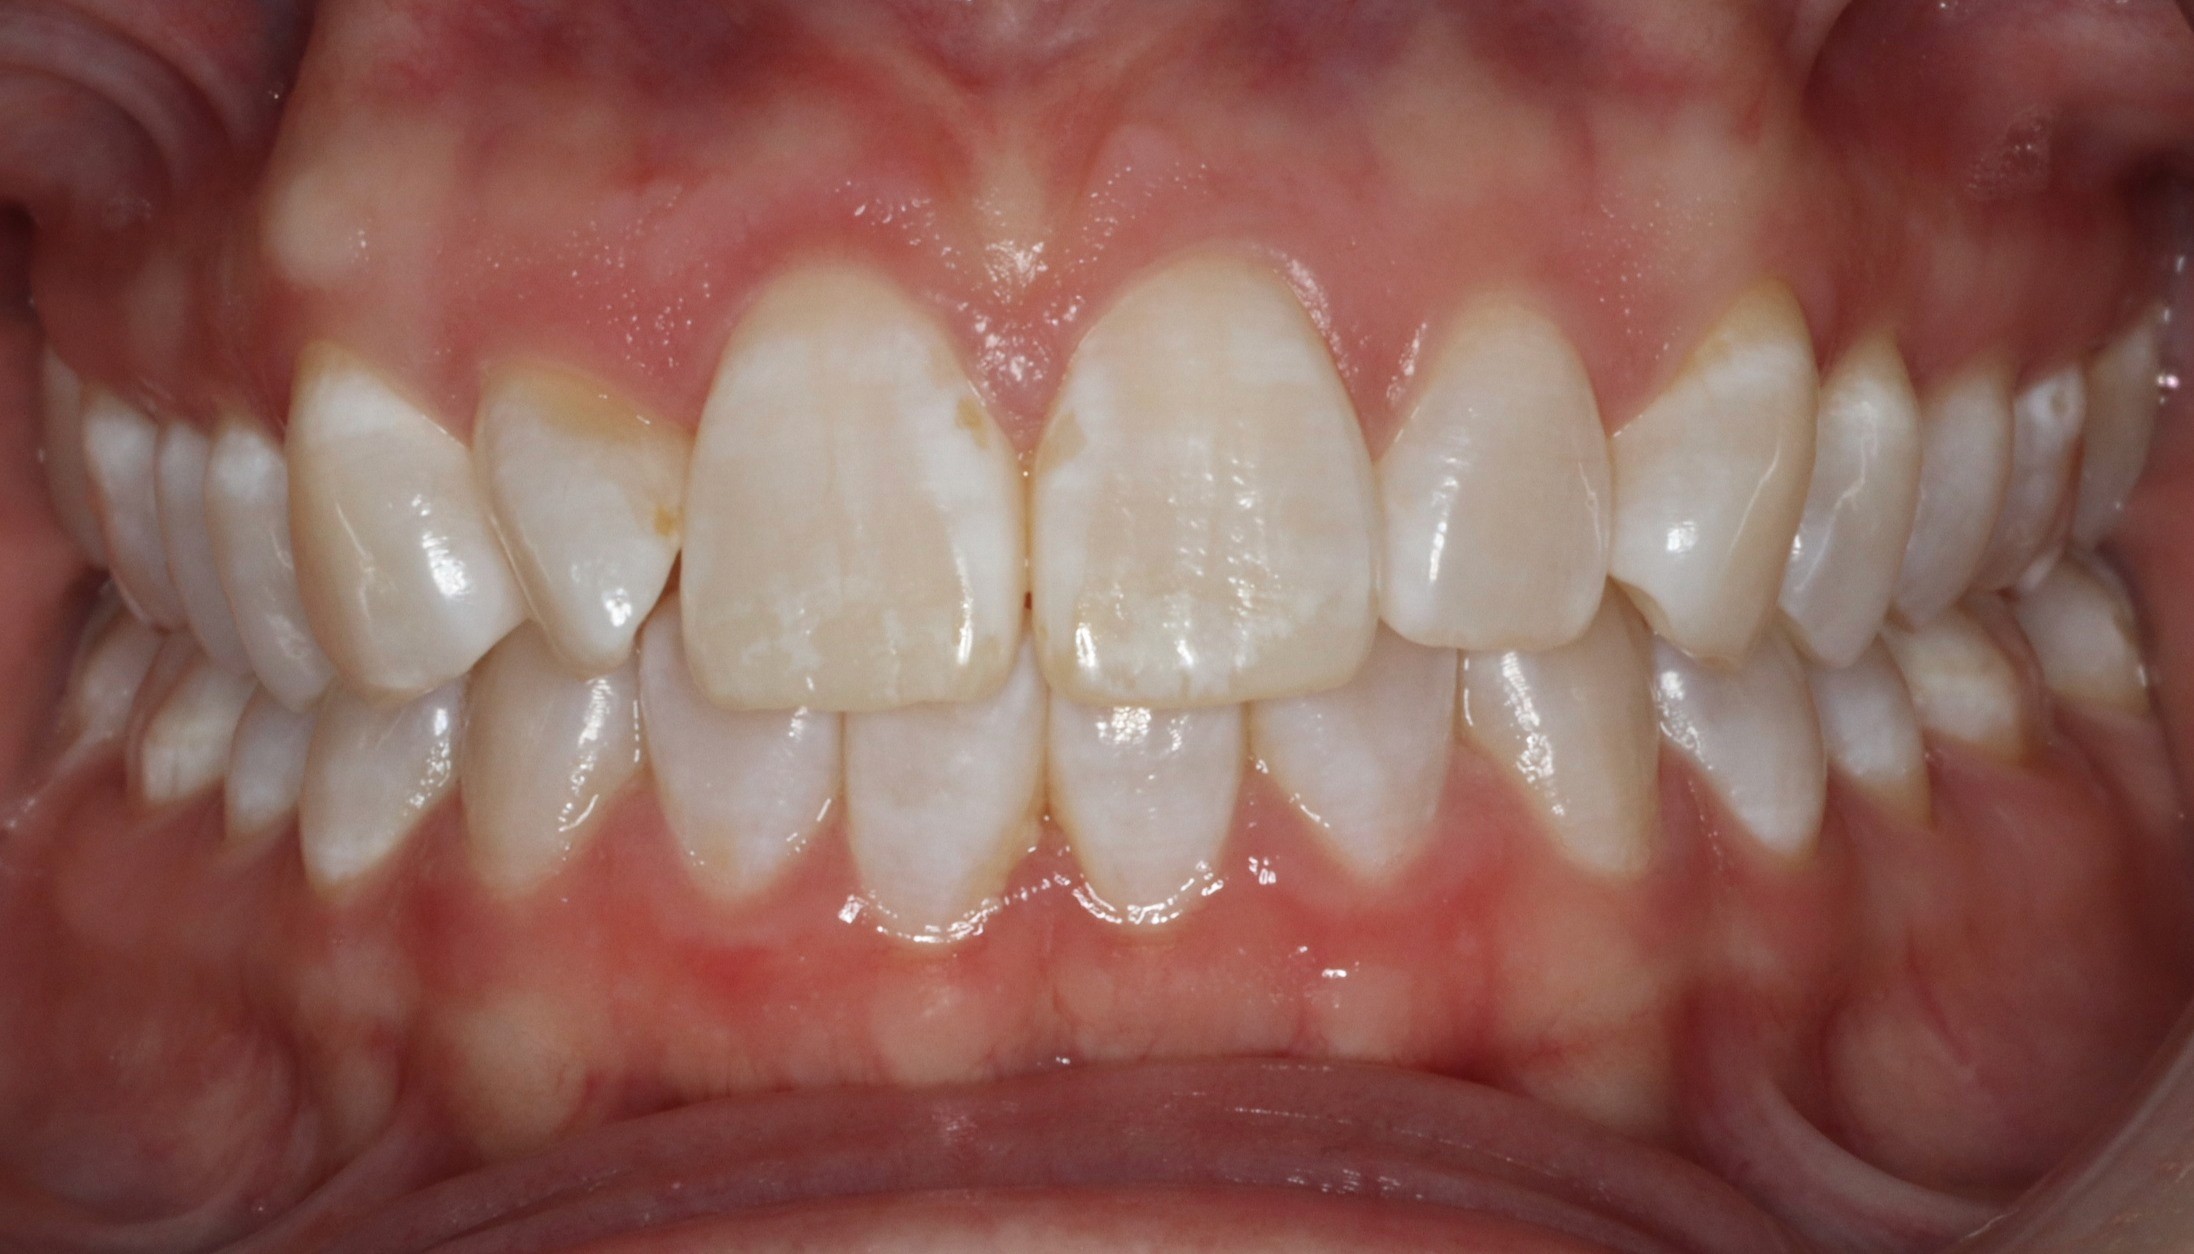

Diagnosis: Deep bite, lower anterior crowding, rotated upper lateral, arch misalignment, wear on teeth from grinding

Initial treatment

INTRAORAL